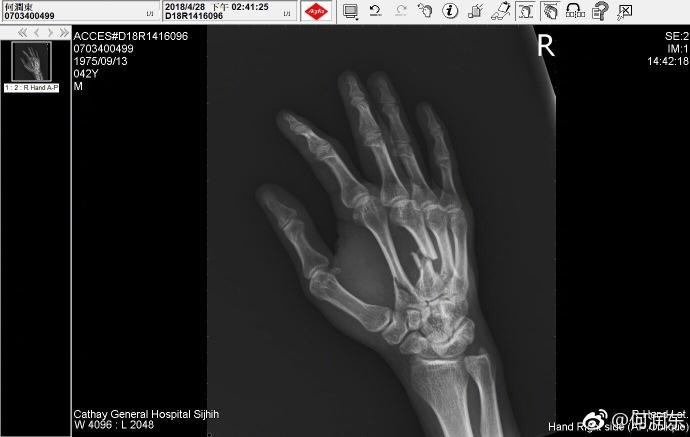

不知道他是在拍戏中受的伤,还是健身中。细看X光拍摄的时间,何润东这次受伤是在4月28日。五一劳动节的时候他还用裹着绷带的手给劳动者致敬,裹这么厚,当时就应该想到他伤得重才是。

前几天才去掉绷带,何润东手背上的两条疤痕又长又清晰,将伴随他一辈子是必然的了。